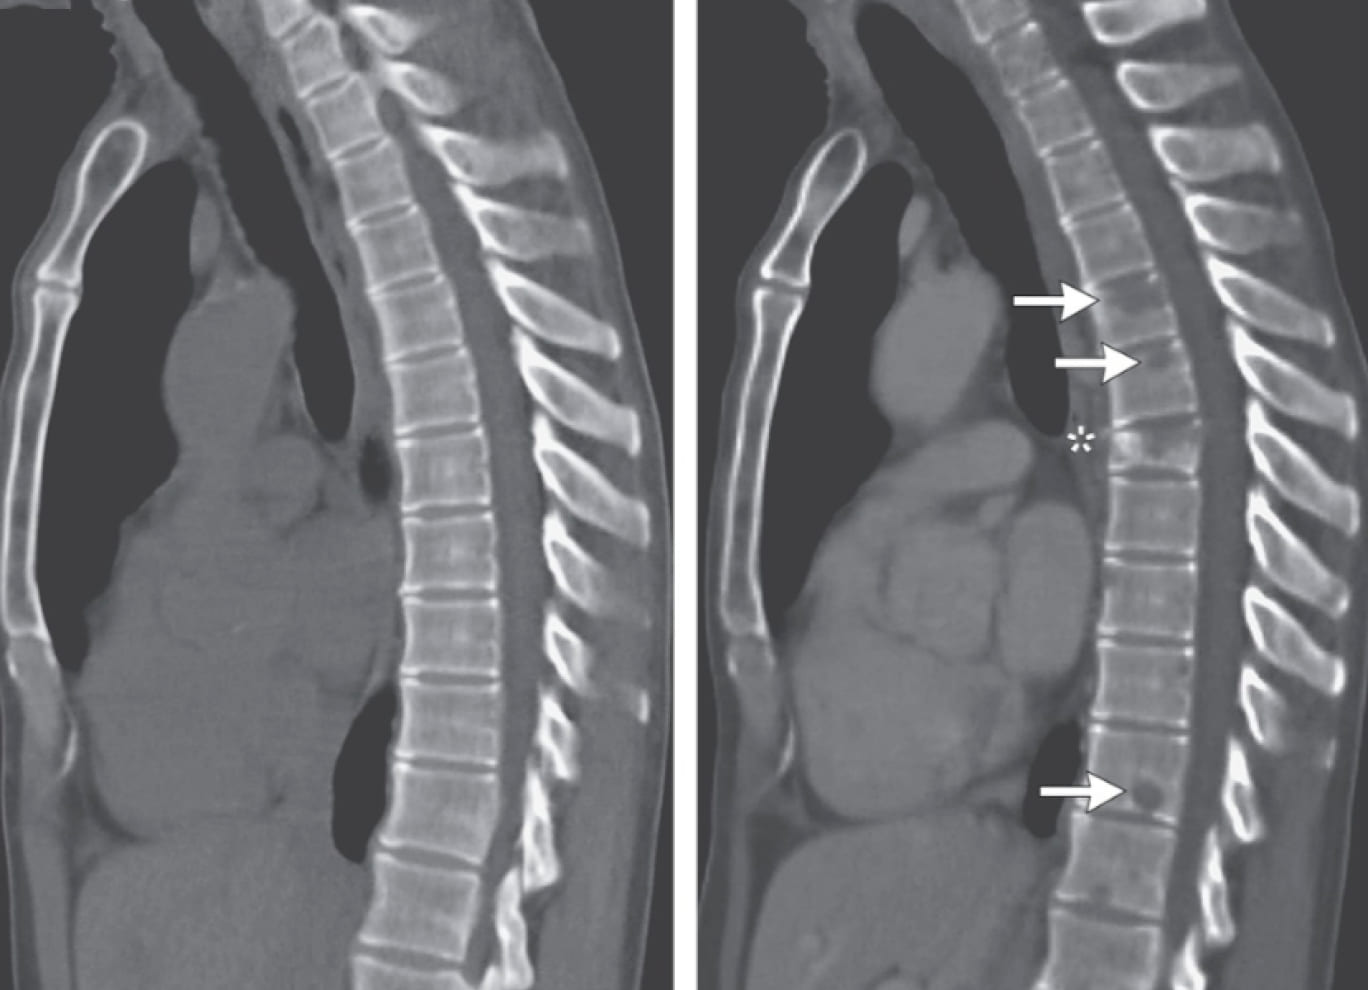

Рис. 1 — МСКТ органов грудной клетки, срез в сагиттальной проекции. В динамике отмечается появление и нарастание остеолитических изменений, ассоциированных с вторичным поражением.

Однако спустя 24 месяца на контрольном обследовании вновь констатировано метастатическое поражение легких, появление новых очагов литического поражения позвоночника.